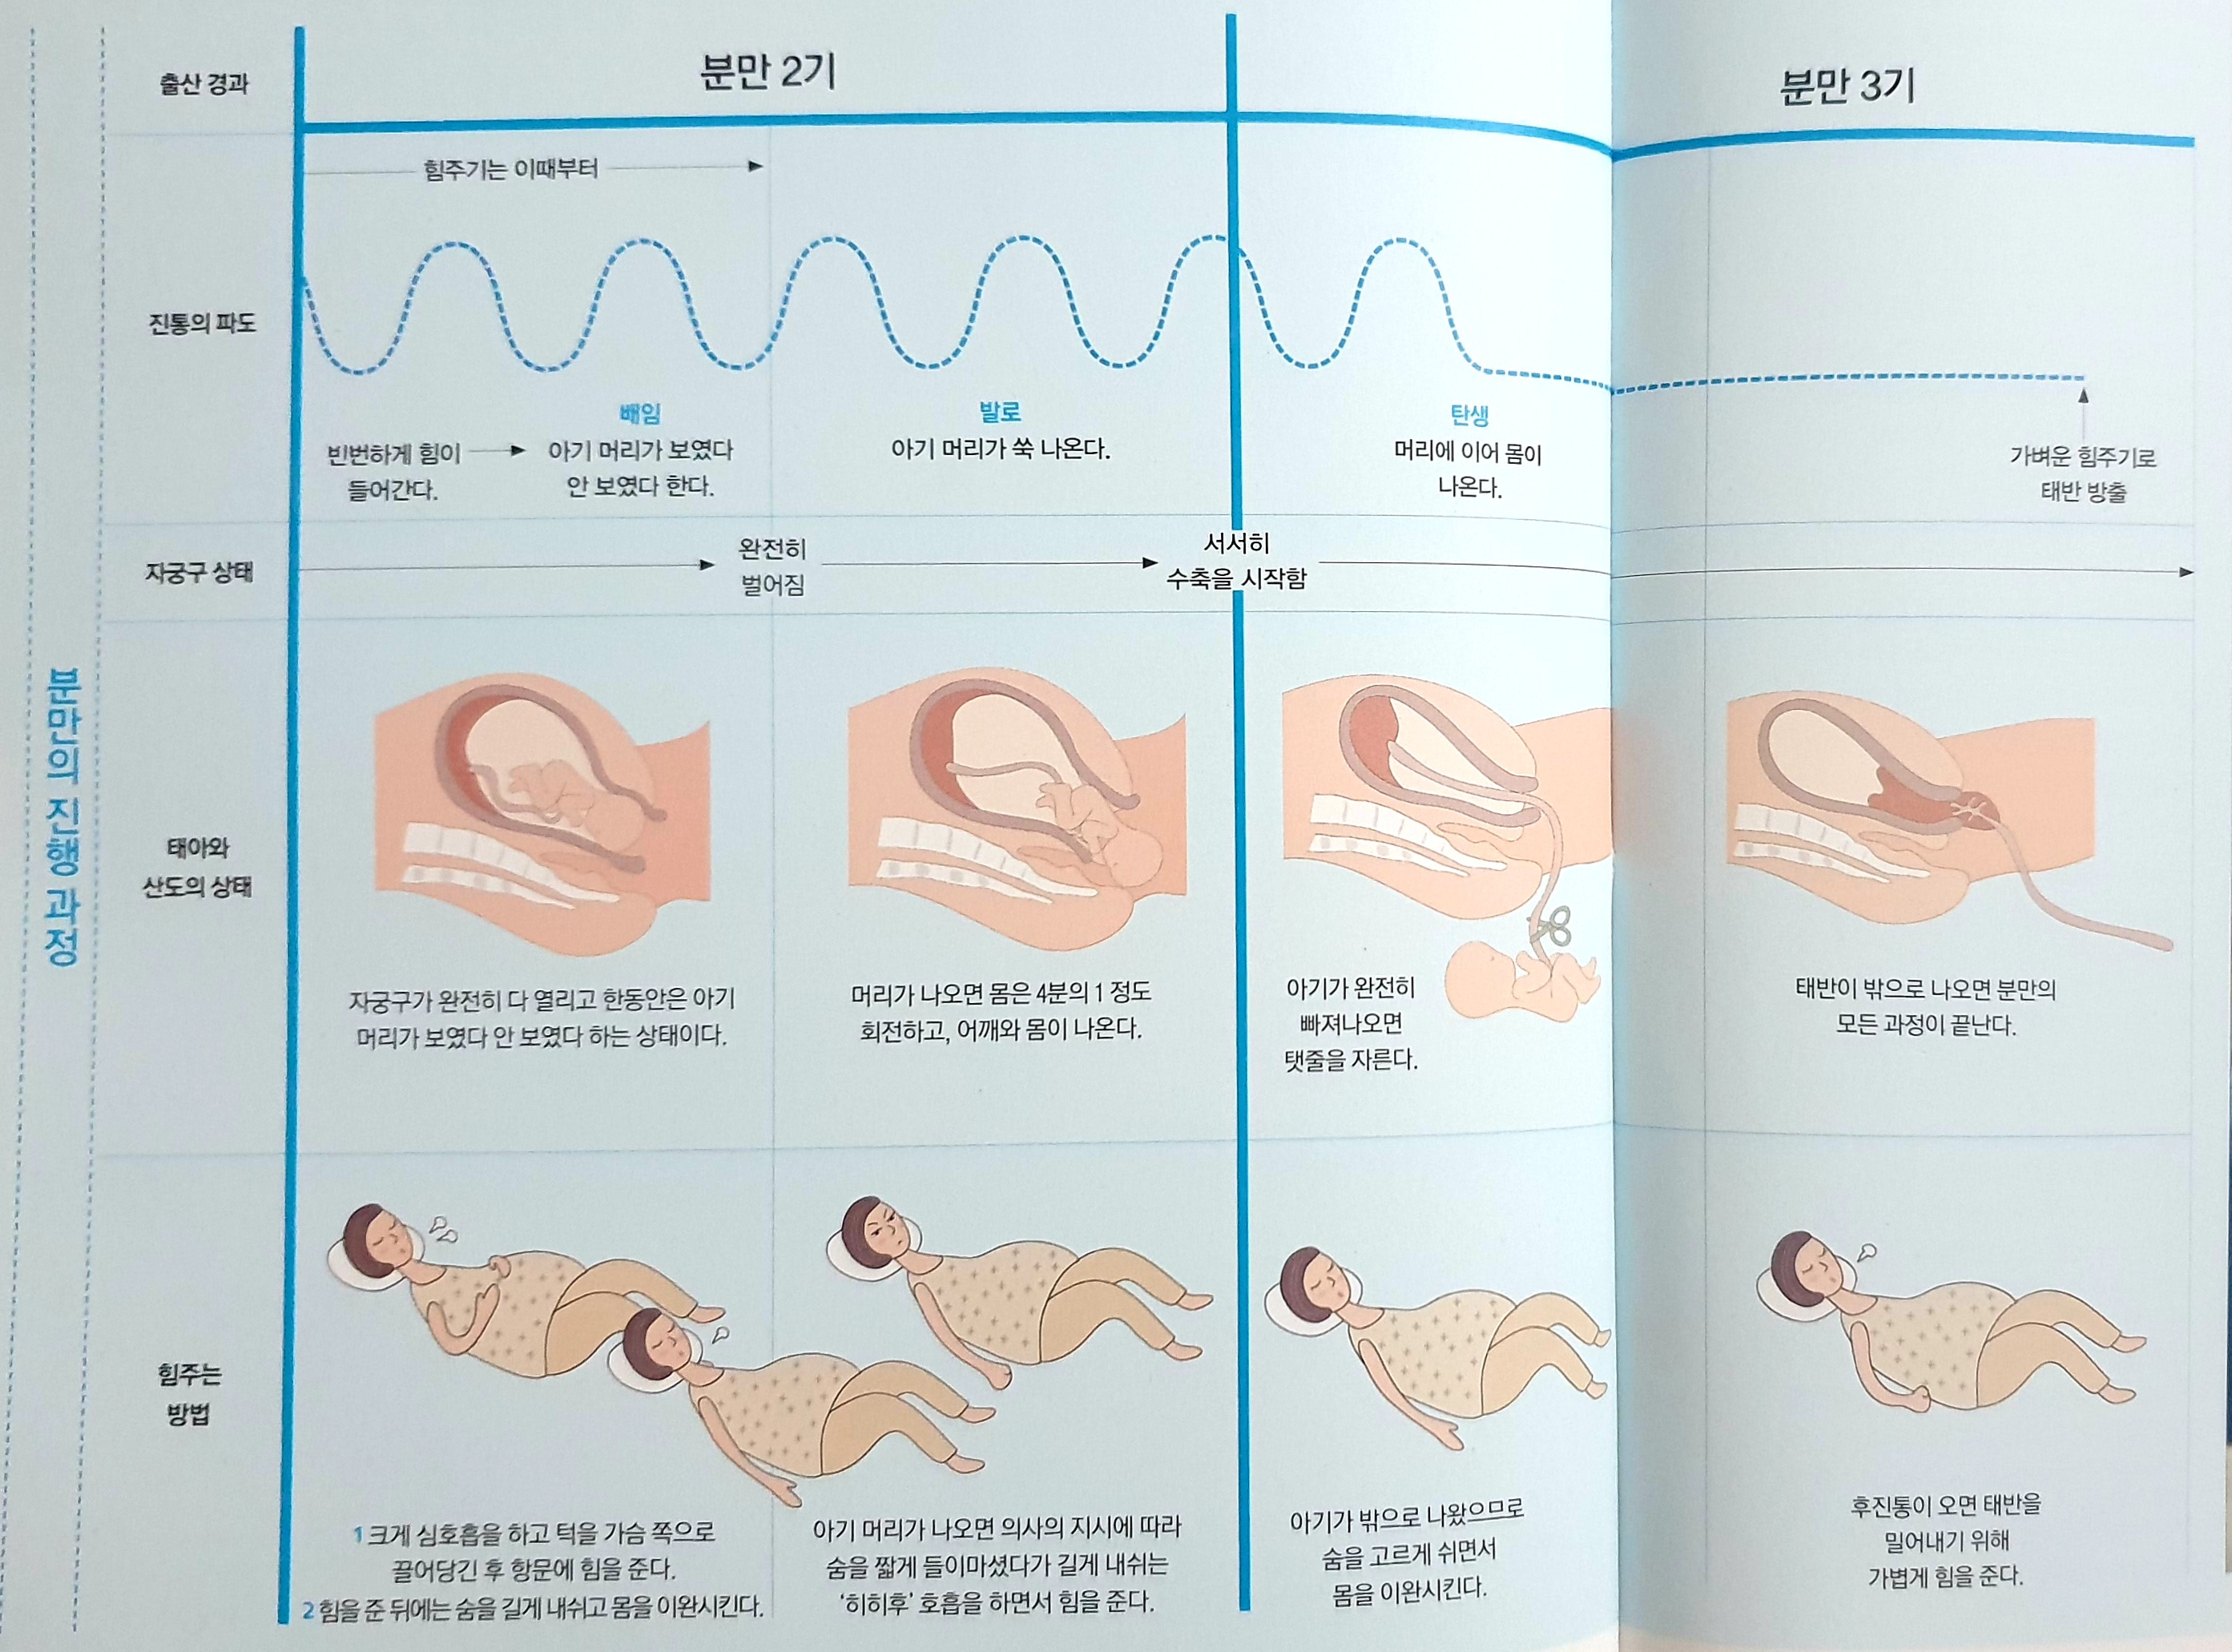

분만 2기 대처법

아기를 밀어낸다

자궁구가 완전히 열리면 아랫배에 힘주고 싶은 느낌이 드는데, 이 시기를 만출기라고 한다. 힘을 주면 아기 머리가 보이다가 주지 않으면 보이지 않는다. 더 진행되면 계속 아기 머리가 보이는데, 이때 무리하게 힘을 주면 회음부가 찢어진다.

마지막까지 힘을 준다

진통은 더 이상 참을 수 없을 정도로 심해져 힘을 주지 않고는 견딜 수 없는 상태가 된다. 그러나 아직 결정적 힘을 주어서는 안 된다. 몸의 힘을 빼고 온몸을 이완시킨다. 의사가 힘을 주라고 지시하면 최대한 숨을 참았다가 길게 힘을 준다. 소리를 지르면 힘이 빠지므로 숨을 참고, 아래쪽에 힘을 준다. 배가 아닌 엉덩이에 힘을 줘야하는데, 배변할 때처럼 항문에 힘을 주면 아기 머리가 나온다. 일단 아기 머리가 나오면 이후에는 힘을 주지 않아도 많은 양의 양수가 쏟아지면서 아기 몸이 쑥 미끄러지며 빠져나온다.

분만 3기 대처법

후진통이 오면 한 번 더 힘을 준다

아기가 자궁에서 모두 빠져나온 후 10분정도 지나면 배 속이 비게 되어 자궁 내의 압력이 급격히 낮아진다. 이때 자궁이 수축하면서 태반이 자궁벽에서 떨어져 나간다. 태반이 몸 밖으로 나오는 것을 후출산, 이때 느끼는 진통을 후진통이라고 한다. 태반은 산모가 가볍게 힘을 주고 의사가 밖에서 탯줄을 살짝 잡아당기면 쉽게 빠져나온다. 태반이 나오면 자궁 수축 주사를 맞는다. 간혹 태반이 자연적으로 배출되지 않는 경우도 있다.